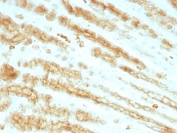

Twenty human keratins are resolved with two-dimensional gel electrophoresis into acidic (pI 6.0) subfamilies. This antibody cocktail recognizes acidic (Type I or LMW) and basic (Type II or HMW) cytokeratins, which include Keratins 1, 3, 4, 5, 6, 8, 10, 14, 15, 16, and 19. Many studies have shown the usefulness of keratins as markers in cancer research and tumor diagnosis. KRTL/KRTH is a broad spectrum anti pan-cytokeratin antibody cocktail, which differentiates epithelial tumors from non-epithelial tumors e.g. squamous vs. adenocarcinoma of the lung, liver carcinoma, breast cancer, and esophageal cancer. It has been used to characterize the source of various neoplasms and to study the distribution of cytokeratin containing cells in epithelia during normal development and during the development of epithelial neoplasms. This antibody stains cytokeratins present in normal and abnormal human tissues and has shown high sensitivity in the recognition of epithelial cells and carcinomas.